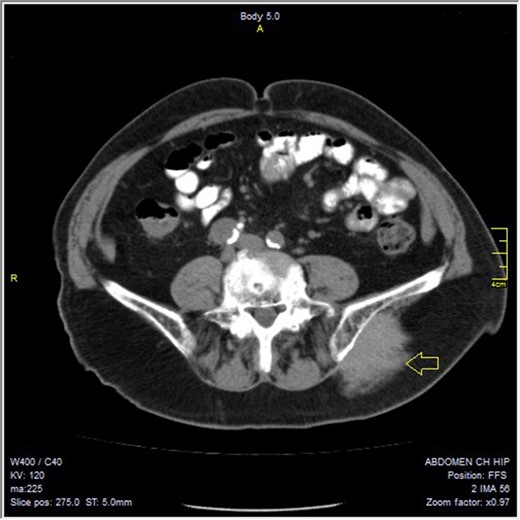

A 79-year-old man was referred to our clinic with a 6-month history of a rapidly growing mass in the left gluteal region. His main complain was pain, radiating down, to the posterior thigh muscles, while in a seated position. He had no previous history of any significant underlying illness, except for gastritis, treated with PPIs and diet. He had also undergone prostatectomy for benign prostatic hyperplasia 2 months before presenting to our clinic. No previous history of trauma in the gluteal or pelvic area was mentioned. At the time of presentation, there was no weight loss, anorexia, fever or other associated symptoms. Physical examination revealed a large, firm, tender mass. Due to rapid growth, the clinical impression was of a malignant neoplasm. Laboratory findings, including lactate dehydrogenase and alkaline phosphatase, were normal. Imaging studies were performed, including pelvic, abdominal and chest computed tomography (CT) and pelvic magnetic resonance imaging (MRI). The CT and MRI examination of the pelvis demonstrated a 7 × 4.4 cm sized soft-tissue mass in the region of left gluteus maximus and gluteus medius muscle. The lesion extended to the surface of the left iliac bone, without infiltrating it (Fig 1). The chest and abdominal CT were performed for detecting metastasis prior to surgery and a CT-guided fine needle aspiration (FNA) biopsy of the mass was performed to determine if the tumor was benign or malignant. The CT was negative for metastasis and the FNA result was inconclusive.